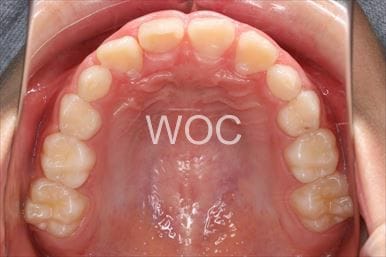

治療後1

治療後2

治療後3

治療後4

治療後5

- 年齢:20歳女性

- 主訴:出っ歯が気になる

- 基本矯正料金:120万円

- 治療期間:1年7ヶ月

- 抜歯部位:上顎両側第一小臼歯